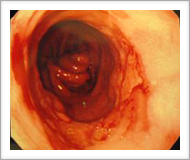

| 胃カメラ検査でも胃と食道のつなぎ目に近い食道粘膜は、ほぼ全周にわたって赤くただれ、粘膜が剥がれ落ち、潰瘍を作っていました(右図)。この潰瘍からは悪性の細胞は見つからなかったので、胃酸が逆流してできた潰瘍と考えられます。 |